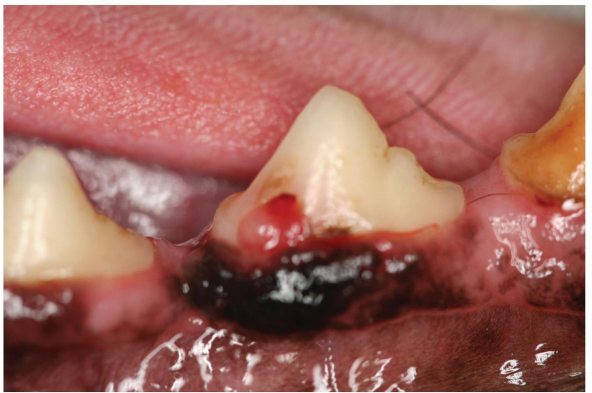

tooth resorption lesion that has reached the crown and granulation tissue as formed a strawberry red uloke